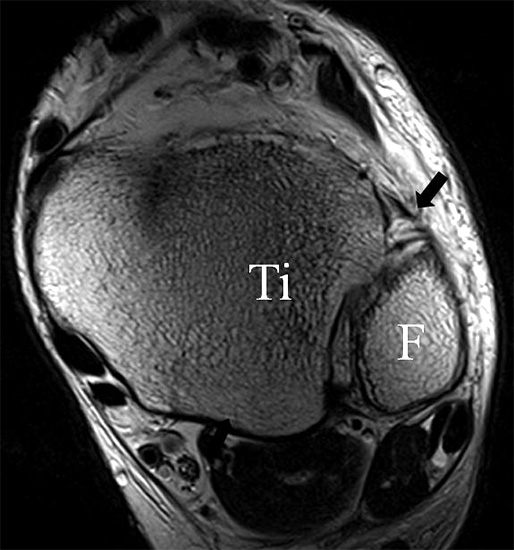

Da also die hintere Syndesmose an der posterioren Tibia inseriert, entspricht eine Fraktur oder Infraktion des hinteren Volkmann`schen Dreiecks funktionell einem knöchernen Ausriss des Ligamentum tibiofibulare posterius (Abb. 18 a und b). Aufgrund der Koinzidenz von Syndesmosenläsionen mit Innenbandverletzungen ist bei der Beurteilung gesondert auf solche zu achten.